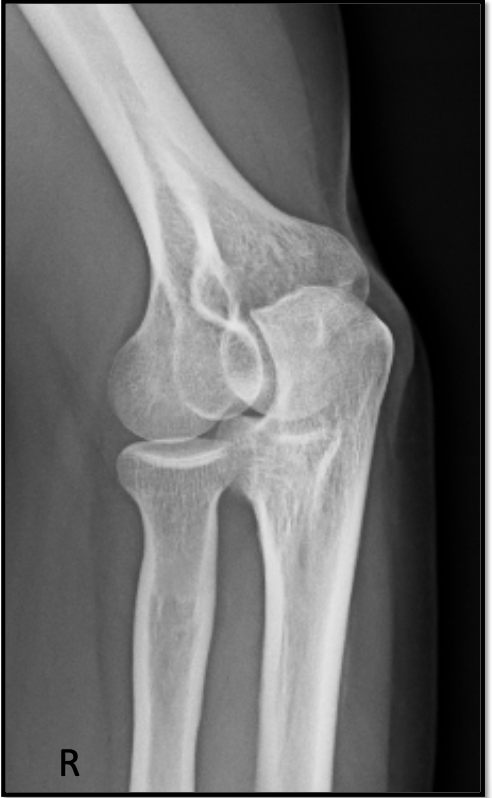

9

Q

AP elbow criteria

A

Medial and lateral humeral epicondyles

are in profile

* 1/4” overlap of radial head on ulna

* 50% of the radius at the radial

tuberosity is superimposed by the ulna

* Capitulum-radial joint space is open

↳have all 3 jointson same plane

* Radius and ulna are parallel

How well did you know this?